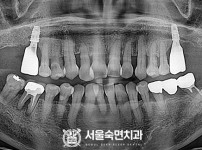

임플란트-전후사진1

치과를-선택할-때-꼭-확인하세요-서울숙면치과-임플란트-전후사진